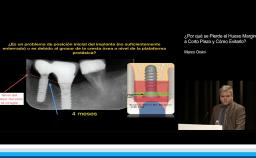

En esta conferencia, la Dra. Iria López habla acerca de las complicaciones que pueden presentarse en prótesis diseñadas con cantiléver. La Dra López lleva su exposición de una forma organizada, en la que primero, fundamenta la relevancia del tema y la frecuencia con la que este tipo de tratamientos se llevan a cabo. Posteriormente hace un análisis tanto de las diferentes circunstancias en las que un cantiléver puede ser utilizado y el tipo de complicaciones protésicas que se pueden presentar. Muestra una excelente selección de artículos que brindan evidencia no solo de las complicaciones protésicas, sino incluso del comportamiento biológico de los implantes que soportan este tipo de prótesis.